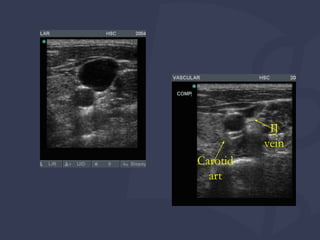

Identificação de artéria vs veia na ultrassonografia

Chave para o sucesso!

VEIAS SÃO:

Compressível

Parede fina e irregular em comparação com a artéria

Não pulsátil (IJ pode ter ondas trifásicas)

Varia com a respiração

Internal

Jugular Vein

IJ

vein

Carotid

art

Interpretação de imagens Identificaçãode artéria vs veia na ultrassonografia Chave para o sucesso! VEIAS SÃO: Compressível Parede fina e irregular em comparação com a artéria Não pulsátil (IJ pode ter ondas trifásicas) Varia com a respiração